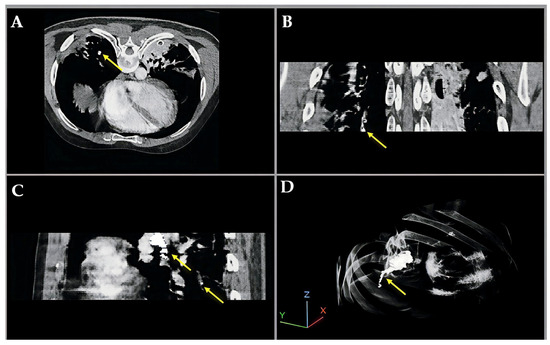

Figure 4 illustrates a pulmonary embolism (PE) detected in a patient’s CT angiography, shown across axial, coronal, sagittal, and 3D views. Yellow arrows highlight the embolus location within the pulmonary artery, demonstrating the value of multi-planar visualization in accurately assessing PE size and position.

Figure 4. Multiview visualization of pulmonary embolism (PE) in CT angiography, illustrating enhanced intensity and fused labeling between the CT image and segmentation results. (A) Axial (XY) view; (B) coronal (XZ) view; (C) sagittal (YZ) view; and (D) 3D volumetric reconstruction.